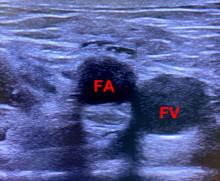

超声引导下股神经联合股动脉阻滞对下肢手术止血带反应的影响

Application of ultrasound⁃guided combined femoral nerve and femoral artery block on tourniquet response in lower extremity surgery

目的 观察超声引导下股神经联合股动脉阻滞减轻膝关节置换术患者止血带反应的安全性与有效性。 方法 选择择期行膝关节置换术治疗的患者100例,年龄18 ~ 75岁,体质量指数18 ~ 30 kg/m2 ,ASA分级为Ⅰ-Ⅲ级;采用随机数字表法随机分为超声引导股神经联合股动脉阻滞组(NA组)和单纯股神经阻滞组(N组),每组50例。两组均在麻醉诱导前行超声引导下目标区域阻滞,待确定阻滞效果后再行麻醉诱导。两组均在喉罩全麻下行手术,术后均予以自控静脉镇痛(PCIA)。术后若患者出现视觉模拟疼痛评分(VAS)> 5分则给予静脉注射氟比洛芬酯50 mg作为补救镇痛。记录患者麻醉前(T1)、止血带充气前1 min(T2)、止血带充气后15 min(T3)、30 min(T4)、45 min(T5)、60 min(T6)的SBP、DBP、HR,记录患者术中发生止血带高血压例数,记录患者术中尼卡地平、艾司洛尔的使用剂量,记录两组术后 2、6、12、24 h的动静态VAS评分,以及术后第1次补救镇痛的时间、补救镇痛的次数、首次下床活动时间和术后恶心、呕吐、谵妄、感染等不良反应发生的情况。 结果 与N组比较,NA组止血带充气后T5、T6时点的SBP、DBP、HR均显著降低,止血带高血压发生率和降压药使用剂量明显降低(P < 0.05),首次下床活动时间提前(P < 0.05);术后两组动静态VAS评分、第1次补救镇痛时间、补救镇痛次数以及术后恶心、呕吐、谵妄、感染等不良反应发生的情况差异无统计学意义(P > 0.05)。 结论 超声引导下股神经联合股动脉阻滞可安全有效地用于减轻膝关节置换术患者止血带反应中,且能够缩短术后首次下床时间,有利于患者的术后康复。

Objective To observe the safety and effectiveness of ultrasound?guided femoral nerve combined with femoral artery block to reduce tourniquet reaction in patients undergoing knee arthroplasty. Methods 100 patients(18 ~ 75 years old, body mass index 18 ~ 30 kg/m2)who were classified as grade Ⅰ?Ⅲ according to ASA standard and received unilateral total knee arthroplasty. The patients were randomly divided into two groups,the ultrasound?guided femoral nerve combined with femoral artery block with general anesthesia was utilized in group NA with 50 cases, and femoral nerve block alone with general anesthesia was used in group N with 50 cases. The target nerve block was guided by ultrasound before induction of anesthesia in both two groups,and anesthesia induction was performed after the block effect was etermined. Patients in two groups underwent surgery under general anesthesia of the laryngeal mask,and all patients under went self?controlled intravenous analgesia(PCIA). If a patient had a visual analogue score(VAS)score > 5 after surgery, flurbiprofenate 50 mg will be given intravenously as a remedy for analgesia. The patients' SBP,DBP and HR were recorded before anesthesia (T1), 1 min before tourniquet inflation (T2), 15 min after tourniquet inflation (T3), 30 min (T4), 45 min (T5), and 60 min (T6),the number of cases of tourniquet hypertension occurring in patients intraoperatively and the amount of nicardipine and esmolol were recorded, and the movement and static VAS scores at 2, 6, 12, and 24 h after surgery were recorded.the postoperative rescue analgesic requirements and the time of getting out of bed were recorded. The incidence of adverse reactions such as nausea,vomiting,deliriumand infection were also recorded. Results Compared with group N,SBP,DBP and HR were significantly lower in group NA at 45 and 60 min after tourniquet inflation, and the incidence of tourniquet hypertension and the amount of nicardipine and esmolol were also significantly lower (P < 0.05), and the time of getting out of bed was advanced (P < 0.05); the movement and static VAS scores,the time of the first remedial analgesia, and number of times of remedial analgesia, as well as the occurrence of nausea,vomiting,delirium and infection were not statistically significant. Conclusion Ultrasound?guided femoral nerve combined with femoral artery block can be safely and effectively used to reduce the reaction of tourniquet in patients with knee arthroplasty, and can shorten the time of getting out of bed after surgery, contributing to promoting postoperative rehabilitation.